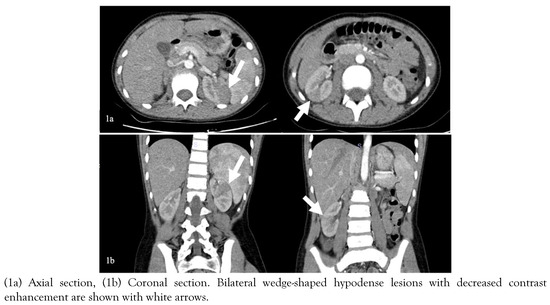

Introduction: Acute suppurative thyroiditis (AST) is an uncommon but potentially life-threatening condition. The majority of AST cases are caused by bacterial infection. Streptococcus suis is a swine pathogen that mostly causes meningitis and septice...